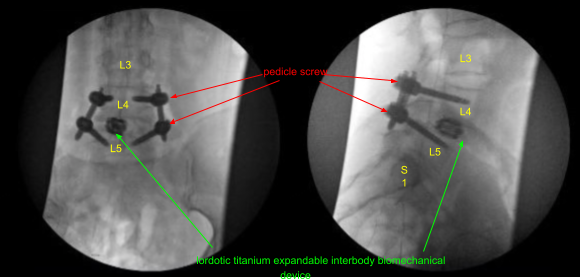

A 22 mm long lordotic titanium expandable interbody biomechanical device was placed through an inserter into the interspace under AP and lateral fluoroscopic guidance and expanded to the proper fit and tightness. The inserter was removed. The tubular retractor was then withdrawn under microscopic visualization to confirm hemostasis with the bipolar electrocautery.

Next, cannulated self-tapping 6.0 x 45 mm titanium pedicle screws were placed over the K-wires at L4 and L5 on the right side under fluoroscopic guidance. K-wires were removed. The screws were advanced until proper tightness was achieved and depth. Neuromonitoring signals were stable throughout. The patient was redraped.

A second intraoperative CT scan was performed showing correct positioning of all of the implanted hardware and instrumentation. Next, calipers were used to determine the length of precut-precontoured titanium rods which were placed across the bilateral L4-5 non segmental pedicle screw instrumentation tulip heads and secured with locking caps.

These were first tightened at L5 bilaterally and then at L4 to achieve reduction of the spondylolisthesis. Approximately 50% reduction was achieved. The locking caps were then final tightened with a torque and anti torque device. The pedicle screw extender tabs were then removed. The wounds were irrigated copiously. Hemostasis was confirmed again.